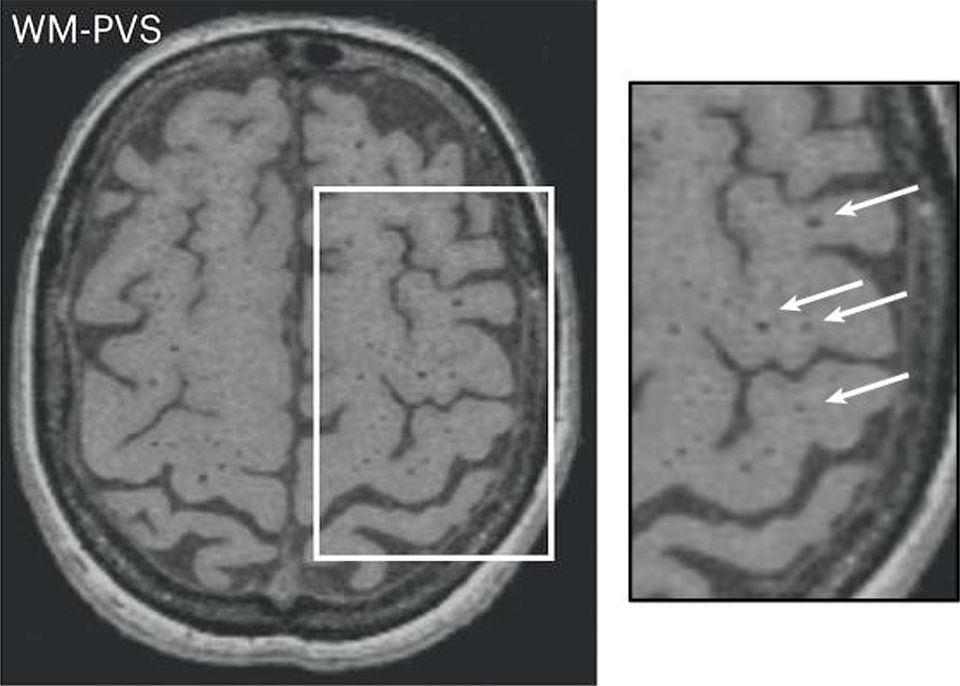

Small Vessel Disease Radiology Key

From radiologykey.com

Small Vessel Disease Radiology Key Reversing Cerebral Small Vessel Disease Cerebral small vessel disease (svd) is a global brain disease affecting multiple. Improved understanding of small vessel disease mechanisms is essential to find ways to prevent damage to the brain, to delay worsening or even reverse the damage, or enhance repair to prevent or delay the damaging clinical consequences of the disease. Cerebral small vessel disease is associated with prehospital. Reversing Cerebral Small Vessel Disease.